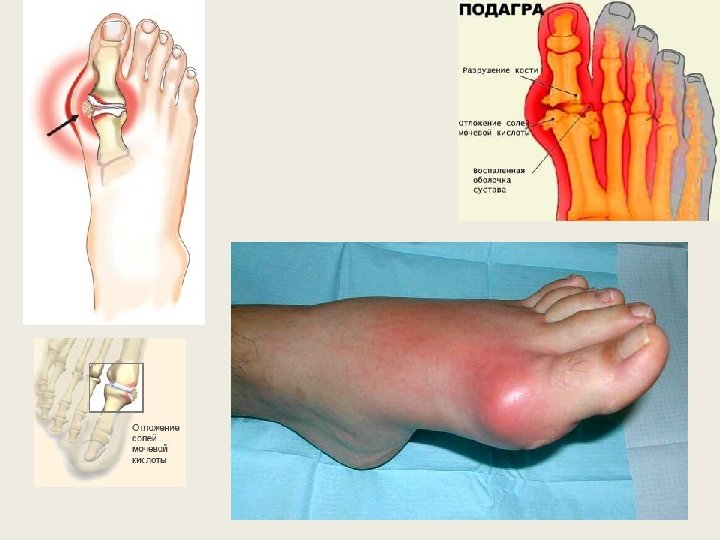

Подагра — это заболевание суставов, которое обусловлено отложением солей мочевой кислоты (уратов). Подагрой страдают примерно три человека из тысячи. Причем мужчины составляют подавляющее большинство. Заболевание обычно проявляется после 40 лет у мужчин и после менопаузы у женщин. Подагра поражает любые суставы: пальцев, кистей, локтей, коленей, ступней. Чаще всего от подагры страдают суставы пальцев ступни. К факторам риска относятся также артериальная гипертония, сахарный диабет, наследственная предрасположенность, нарушение питания. Как правило, приступ подагры развивается на фоне приема алкоголя (особенно пива) или переедания. Заболевание проявляется внезапной и интенсивной болью, покраснением и «жаром» в суставе. Приступы подагры случаются, как правило, ночью. Острая боль в пораженном суставе может быть вызвана даже весом простыни. Повторному приступу подагры обычно предшествует ощущение покалывания в пораженном суставе. Если подагру не лечить, приступы становятся чаще, а периоды обострения продолжительнее. Артрит обживает все новые суставы,